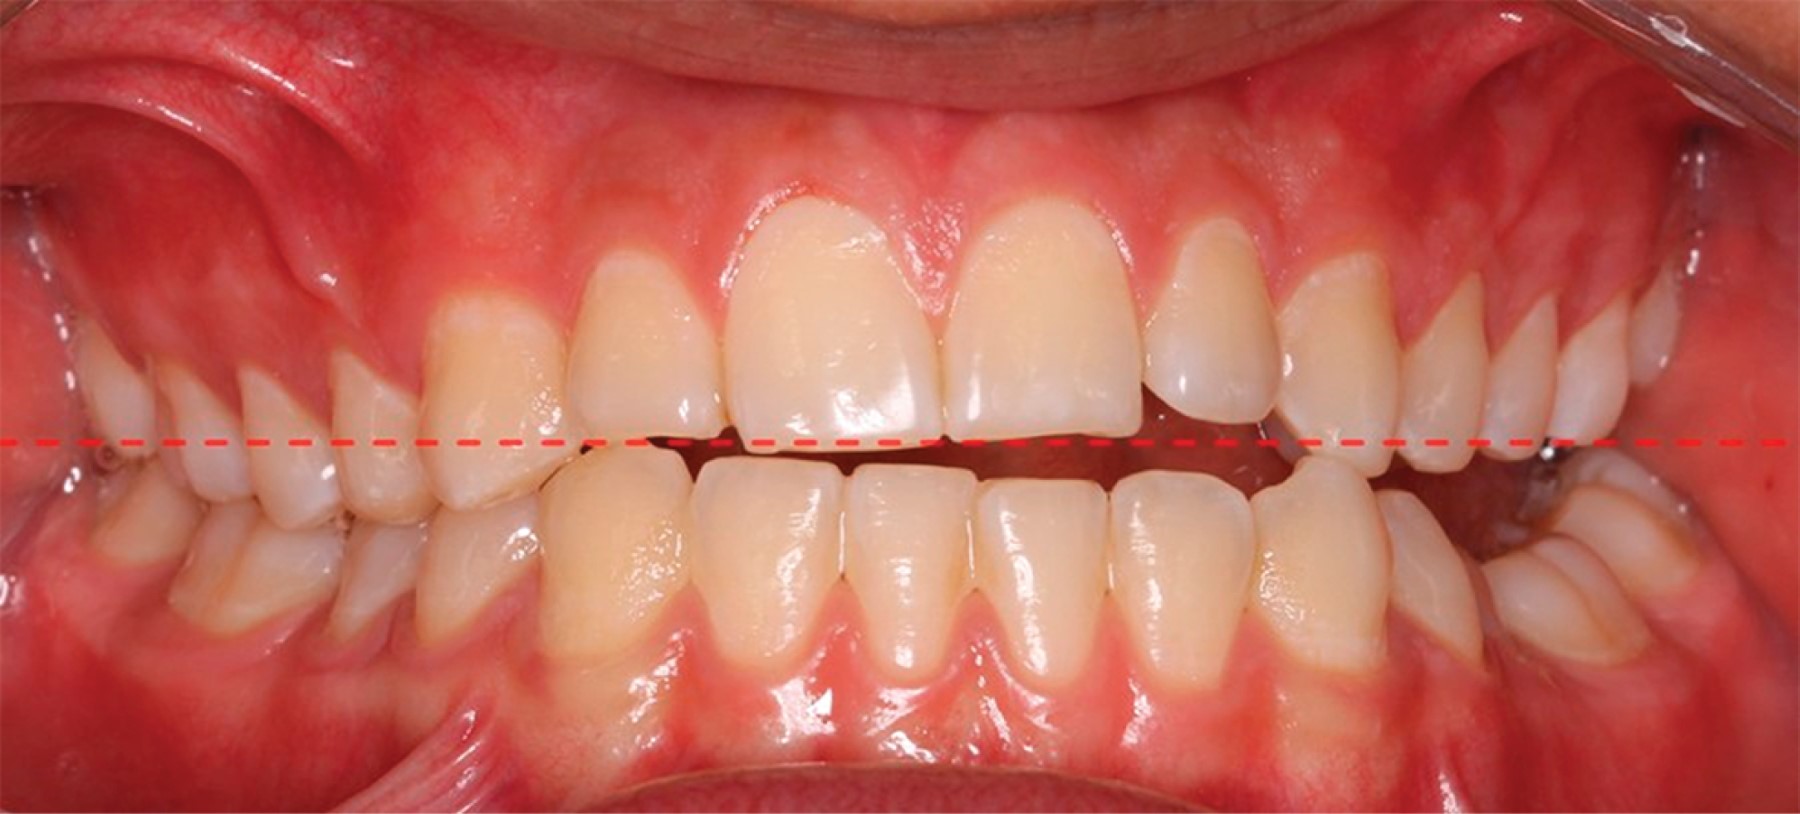

Tenemos que entender que el asentamiento del plano oclusal es una estructura funcional primordial y no sólo es una consideración estética. La literatura considera que la exposición de encía del maxilar superior debe ser de 0-2 mm en sonrisa y que los bordes incisales de los dientes superiores deben mostrarse de 2-4 mm cuando el labio se encuentra en reposo. Sin embargo, debemos tener ciertas consideraciones como que los incisivos superiores disminuyen su exposición con la edad, es decir, los pacientes jóvenes tienen mayor exposición de los dientes superiores, mientras que los adultos muestran más los dientes inferiores. Estas consideraciones son muy importantes y deben tomarse en cuenta al momento de determinar qué tipo de plano oclusal estético funcional (POEF) queramos dejar, de acuerdo con la edad del paciente (Figura 3).10,11

La forma e inclinación del plano oclusal así como sus características individuales están relacionadas con la función del sistema estomatognático, al igual que con la estética dentofacial. Es muy importante determinar cuál es el plano oclusal en el que se basará la interpretación diagnóstica o terapéutica del paciente, ya que además de tener diferentes planos oclusales dentro de la misma boca, por ejemplo, el plano oclusal funcional (POF) o el plano oclusal bisectado (PLB), encontramos diferencias de asentamiento oclusal en pacientes clase II y III o en pacientes con crecimiento vertical y crecimiento horizontal.7,11-13